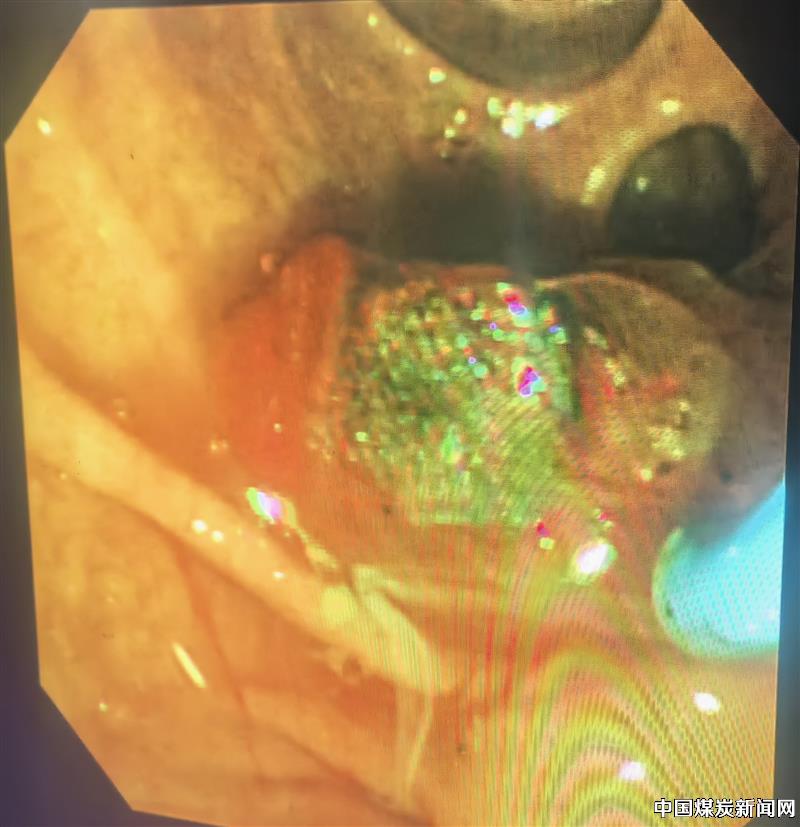

患者85岁,不仅基础疾病多,还伴有感染性休克、酸碱平衡紊乱、电解质紊乱、低蛋白血症等,均增加了手术风险。救与不救风险都很高,面对这样的两难问题,刘大夫、李主任会商后决定冒险一搏。经过耐心向患者家属交代病情及手术风险,并取得同意后,急诊行ERCP术。术中见大量脓液流出,证实了术前诊断,手术过程顺利,术后患者病情逐步恢复正常。